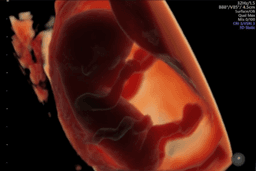

A bill mandating insurance coverage for fertility treatments has passed a Minnesota Senate committee, marking a significant step forward for families advocating for this legislation. The proposal aims to ensure that individuals diagnosed with infertility can access necessary treatments without facing prohibitive out-of-pocket expenses.

Supporters emphasize that without insurance mandates, the ability to start a family is tied to financial capacity, a disparity many witness daily. Personal testimonies from advocates detail the arduous and costly journeys to parenthood, involving multiple miscarriages and expensive IVF treatments borne without insurance.